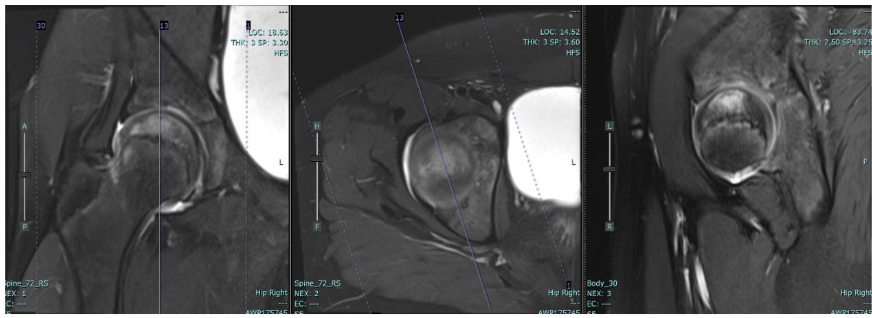

The location of overuse injuries can vary depending on the specific sport and the individual’s biomechanics. This case report discusses a rare instance of femoral head insufficiency fracture in a young gymnast, highlighting the need for awareness and early diagnosis in similar cases.

Diagnosing overuse injuries can be challenging, as they may mimic other conditions. Early recognition and intervention are critical to prevent long-term complications. In this case, the young gymnast presented with hip pain that was initially attributed to overtraining.